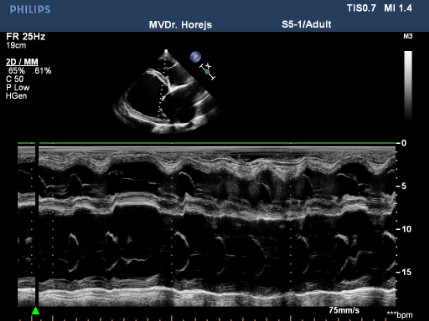

Dilatační kardiomyopatie